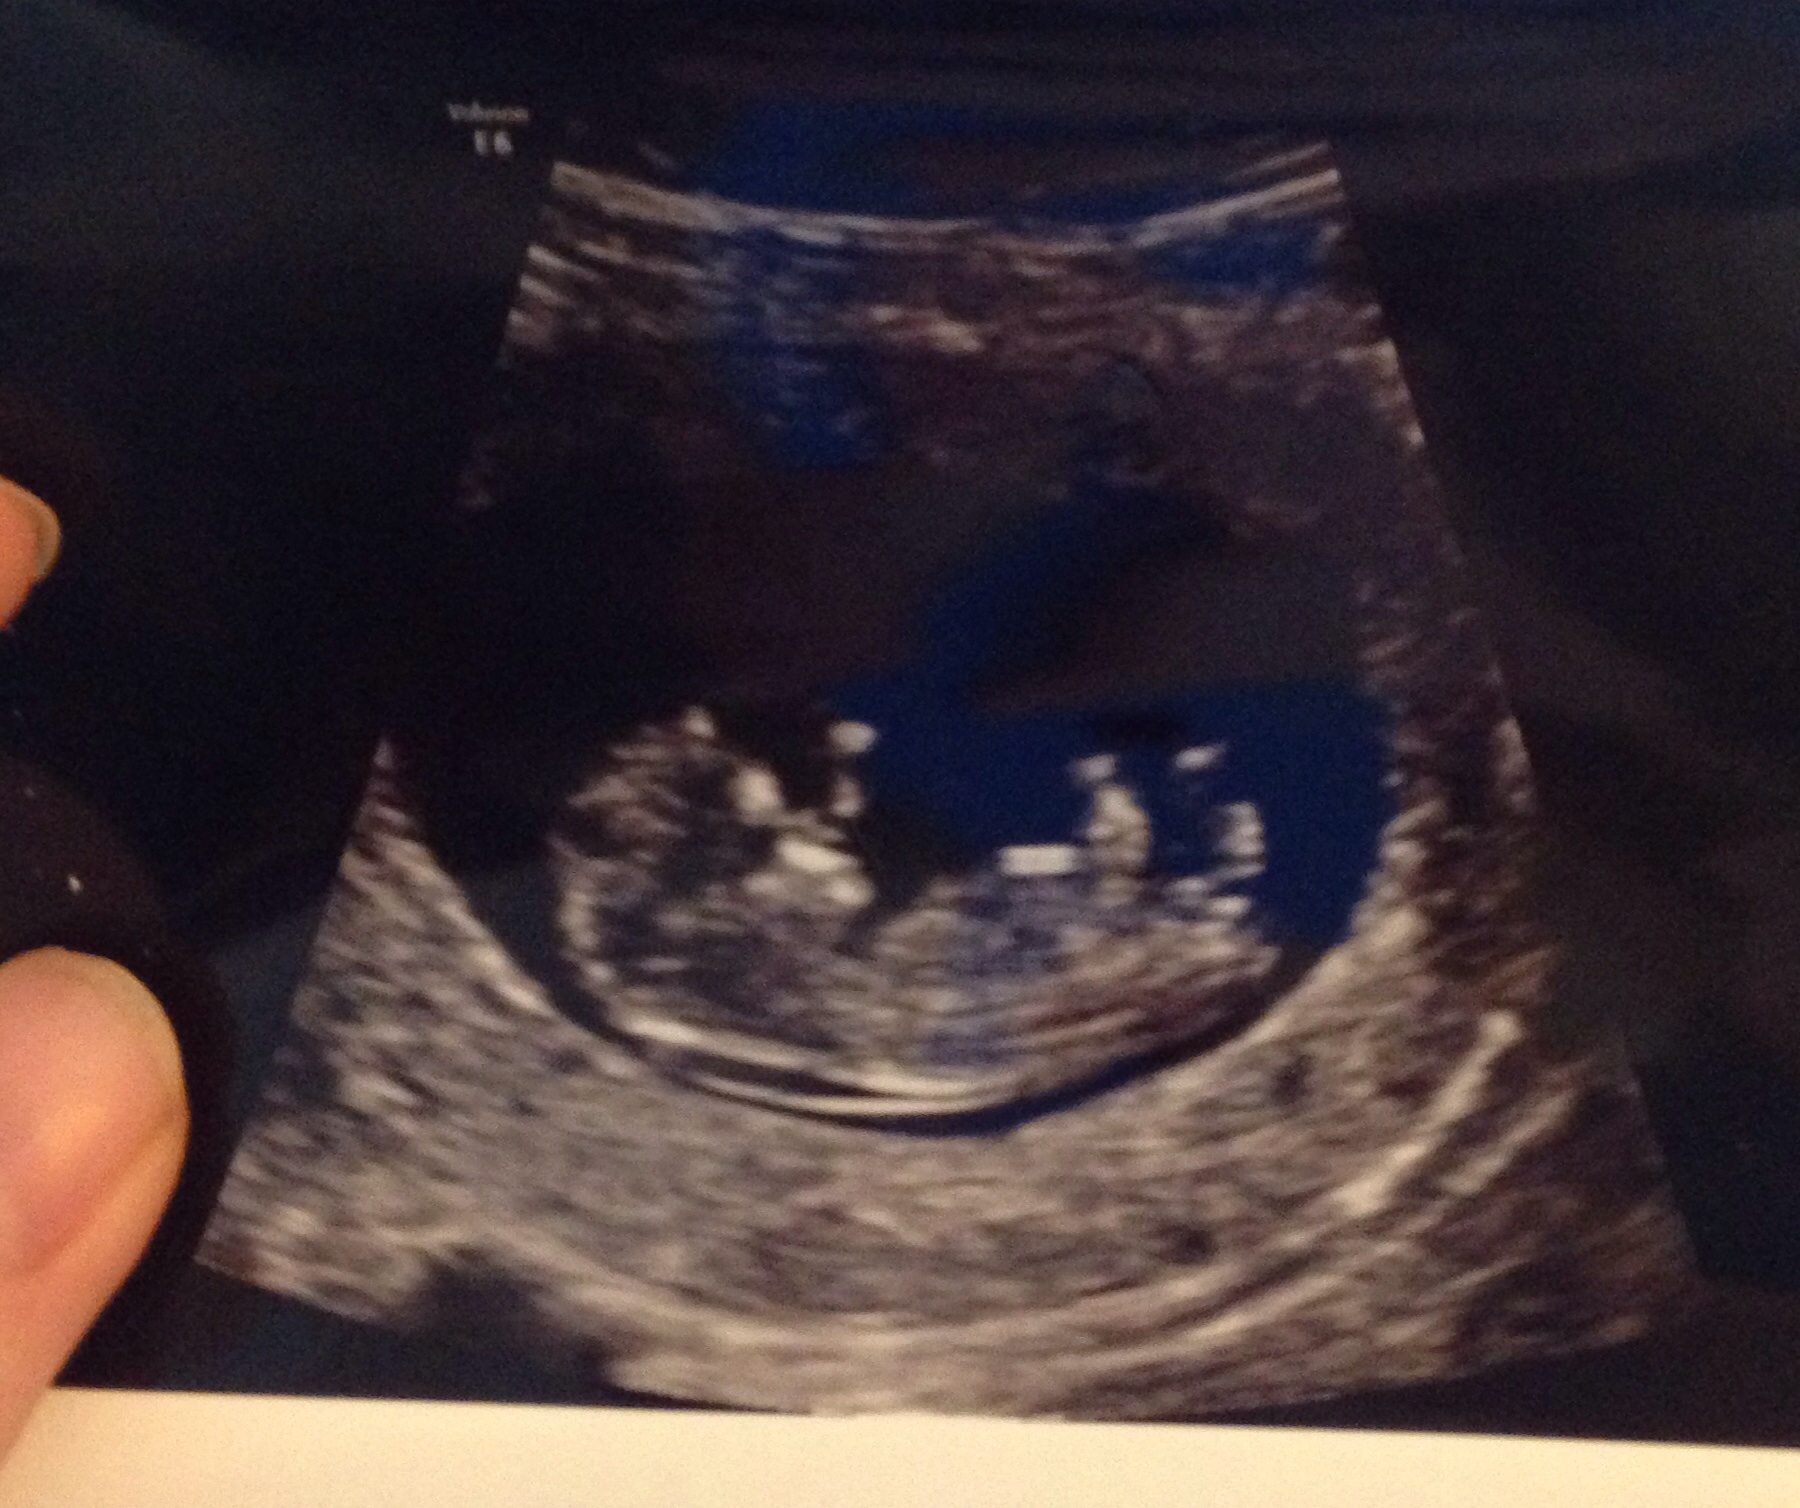

What do you think? Boy? Girl?Attachment 26581

Maybe boy.

boy lean

Baby looks pretty young, what gestation is it :) Leaning slightly boy at this point.